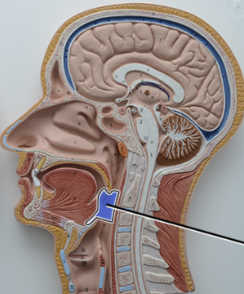

What structure is this?

Diaphragm

What structure is this?

Hard Palate

What structure is this?

Soft Palate

What structure is this?

Uvula

What structure is this?

Nasal cavity

What structure is this?

Superior Nasal Concha

What structure is this?

Middle Nasal Concha

What structure is this?

Inferior Nasal Concha

What structure is this?

The nasopharynx region of the pharynx

What structure is this?

The Oropharynx region of the pharynx

What structure is this?

The Laryngopharynx region of the pharynx

What structure is this?

Thyroid Cartilage

Nasal Septum